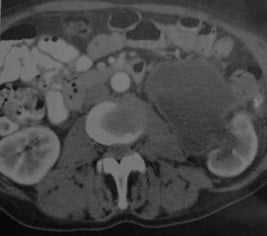

В каких случаях проводят КТ брюшной полости с контрастом при пионефрозе

- КТ показана только в том случае, если УЗИ не позволяет установить диагноз

- КТ с внутривенным контрастированием

- Утолщение стенок чашечно-лоханочной системы

- КОРИ 20-30 ЕХ позволяет заподозрить наличие гноя или инфицированной мочи

- Наличие осадка из тканевого детрита

- При многофазной КТ (КТ с внутривенной пиелографией, которая выполняется с использованием низкодозной техники) определяется отсутствие экскреции КВ («немая» почка).

Пионефроз слева. Аксиальная многослойная КТ в кортикальной фазе. Расширение почечной лоханки и чашечек с утолщением стенок. КОРИ жидкости около 30 ЕХ.